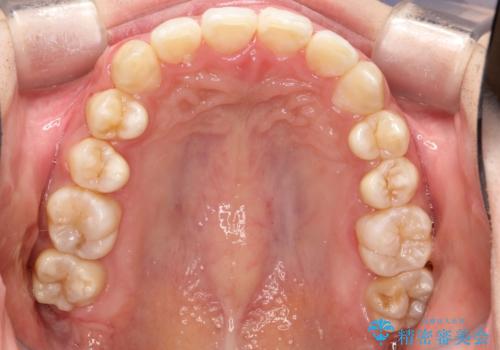

重度のガタガタのインビザラインによる非抜歯矯正

- 全体的なガタガタを気にされて来院されました。

抜歯矯正も考えられる状態でしたが、ご本人的になるべく歯を抜かない矯正を希望されました。

奥歯を後方に移動させるのと、歯と歯の間にわずかに隙間を作ることでスペースを確保して、抜歯をせず歯を並べる計画としました。

ガタガタの度合いが大きかったので少し時間がかかりましたが、非常に協力的な患者様でしたので、抜歯をせず計画通りに治療を終えることができました。